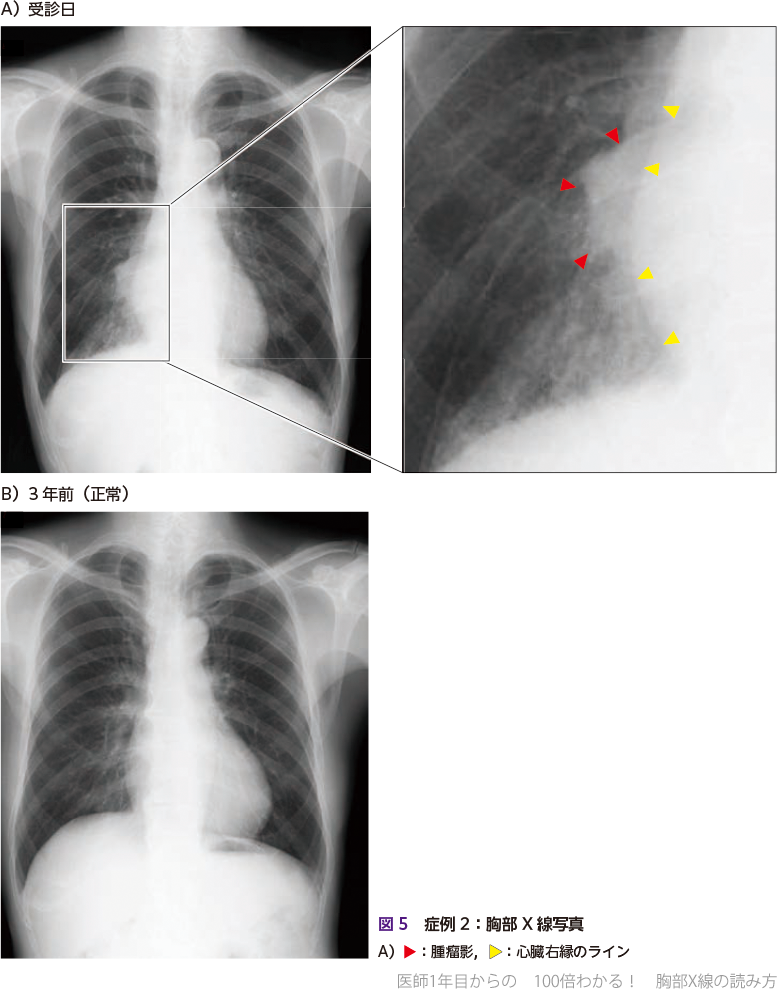

1カ月前からの咳,数日前からの血痰を主訴に受診

まず胸部X線写真を撮影しました(図5A).右肺門部に心臓と重なる腫瘤影を認めます(図5A右

).3年前に施行された胸部X線写真(図5B)では,該当する病変はありません.

腫瘤影と重なる領域における心臓右縁(右第2弓)の「線」は明瞭であり (図5A右

),心臓右縁に対するシルエットサインは陰性と判断します.X線写真上は重なって見えても,実際には心臓から離れた区域に存在している病変と推察されます.